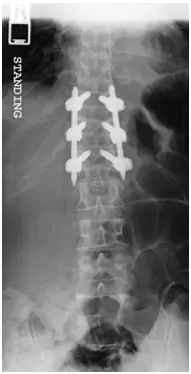

The fracture was stabilized by Minimal Invasive spine surgery with percutaneous pedicle screws in T11, 12 and L1 and rod fixation.

Patient tolerated the procedure well. She was pain free after the surgery and discharged home after 1 day. She was able to return to her usual activities in about 8 weeks.